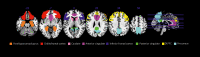

Figure 2.

Figure 2.. Regions that showed activation in response to internet and videogame cues in internet gaming disorder (IGD) participants in more than two studies. DLPFC, dorsolateral prefrontal cortex. Reproduced from ref 6: Weinstein A, Livny A, Weizman A. New devel­opments in brain research of internet and gaming disorder. Neurosci Biobehav Rev. 2017;75:314-330. Copyright © Elsevier 2017